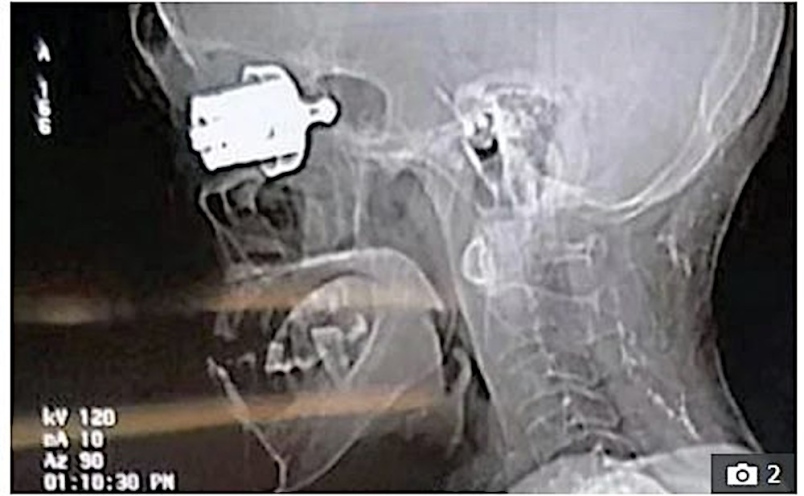

IMBASAN tomografi berkomputer menunjukkan wisel periuk tekanan di dalam tengkorak mangsa.

Petugas kecemasan tidak dapat melihat serpihan sebesar sebutir peluru itu dari luar tetapi pakar bedah berjaya menariknya keluar tidak lama kemudian.